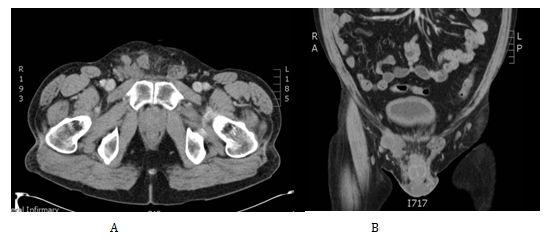

We present the case of a 52-year-oldman that presented initially in our urology clinic with a 2-year history of a lump on his right testicle. His past medical history included a perforated duodenal ulcer at age seventeen, hypertension and a current smoker of twenty per day but no previous history of asbestos exposure. He denied any change in size, shape or consistency of the lump during this time. On examination his abdomen was soft not tender. The left testis felt normal while there was a right sided hydrocele. Separate from the right testicle there was a hard, irregular mass which was mobile and not tender. An urgent US scan was organised from clinic (Figure 1), this confirmed a 20mmx 15mm x 17mm vascular mass, adjacent to and possibly arising from the superior right spermatic cord.

Figure 1 Ultrasonographic appearances of the tumour.

A: A is a 2cm x 1.7cm x 1.5cm heterogeneous lesion arising from or adjacent to the right spermatic cord.

B: Here it is shown clearly to be separate from the right testis and epididymis.

C: Doppler study confirmed a solid component with some internal vascularity.